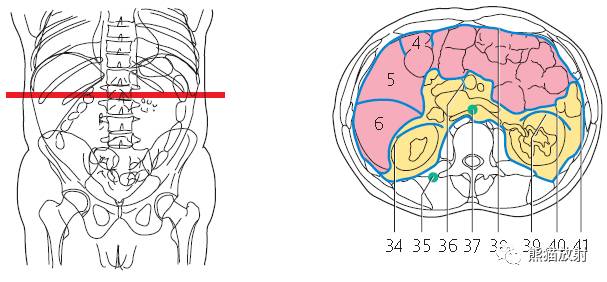

第九层

1、肝脏;2、右肾动脉;3、胆囊;4、结肠右曲;5、十二指肠;6、腹直肌;7、下腔静脉;8、肠系膜上动脉及静脉;9、横结肠;10、十二指肠空肠曲;11、腹主动脉;12、空肠及回肠动/静脉;13、左肾静脉;14、空肠;15、降结肠;16、内斜肌;17、外斜肌;18、肾皮质;19、肾盂;20、最长肌;21、膈肌;22、胸椎;23、棘肌;24、椎管;25、腰动/静脉;26、腰大肌;27、左睾丸动脉;28、腰方肌;29、左肾动脉;30、髂肋肌;31、肾锥体;32、背阔肌;33、肝肾隐窝;34、肾门;35、肋间淋巴结;36、腰淋巴结;37、大网膜;38、肠系膜根部;39、左侧肠系膜结肠沟;40、左侧结肠旁沟。